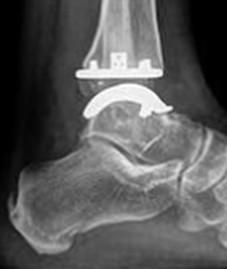

Moderne Sprunggelenksprothesen bestehen meist aus mehreren Komponenten aus Metall und einem beweglichen Kunststoffkern. Sie ahmen die natürliche Bewegung des Gelenkes nach und sollen eine möglichst gleichmäßige Belastung ermöglichen.

Die Abbildungen zeigen eine Endoprothese des oberen Sprunggelenkes. Sie ist ein sogenannter Oberflächenersatz (Resurfacing). Dieses Implantat wird zementfrei eingesetzt.